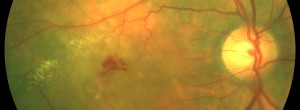

Hyporeflective wedge-shaped band in geographic atrophy secondary to age-related macular degeneration: a little-understood spectral domain optical coherence tomography finding.